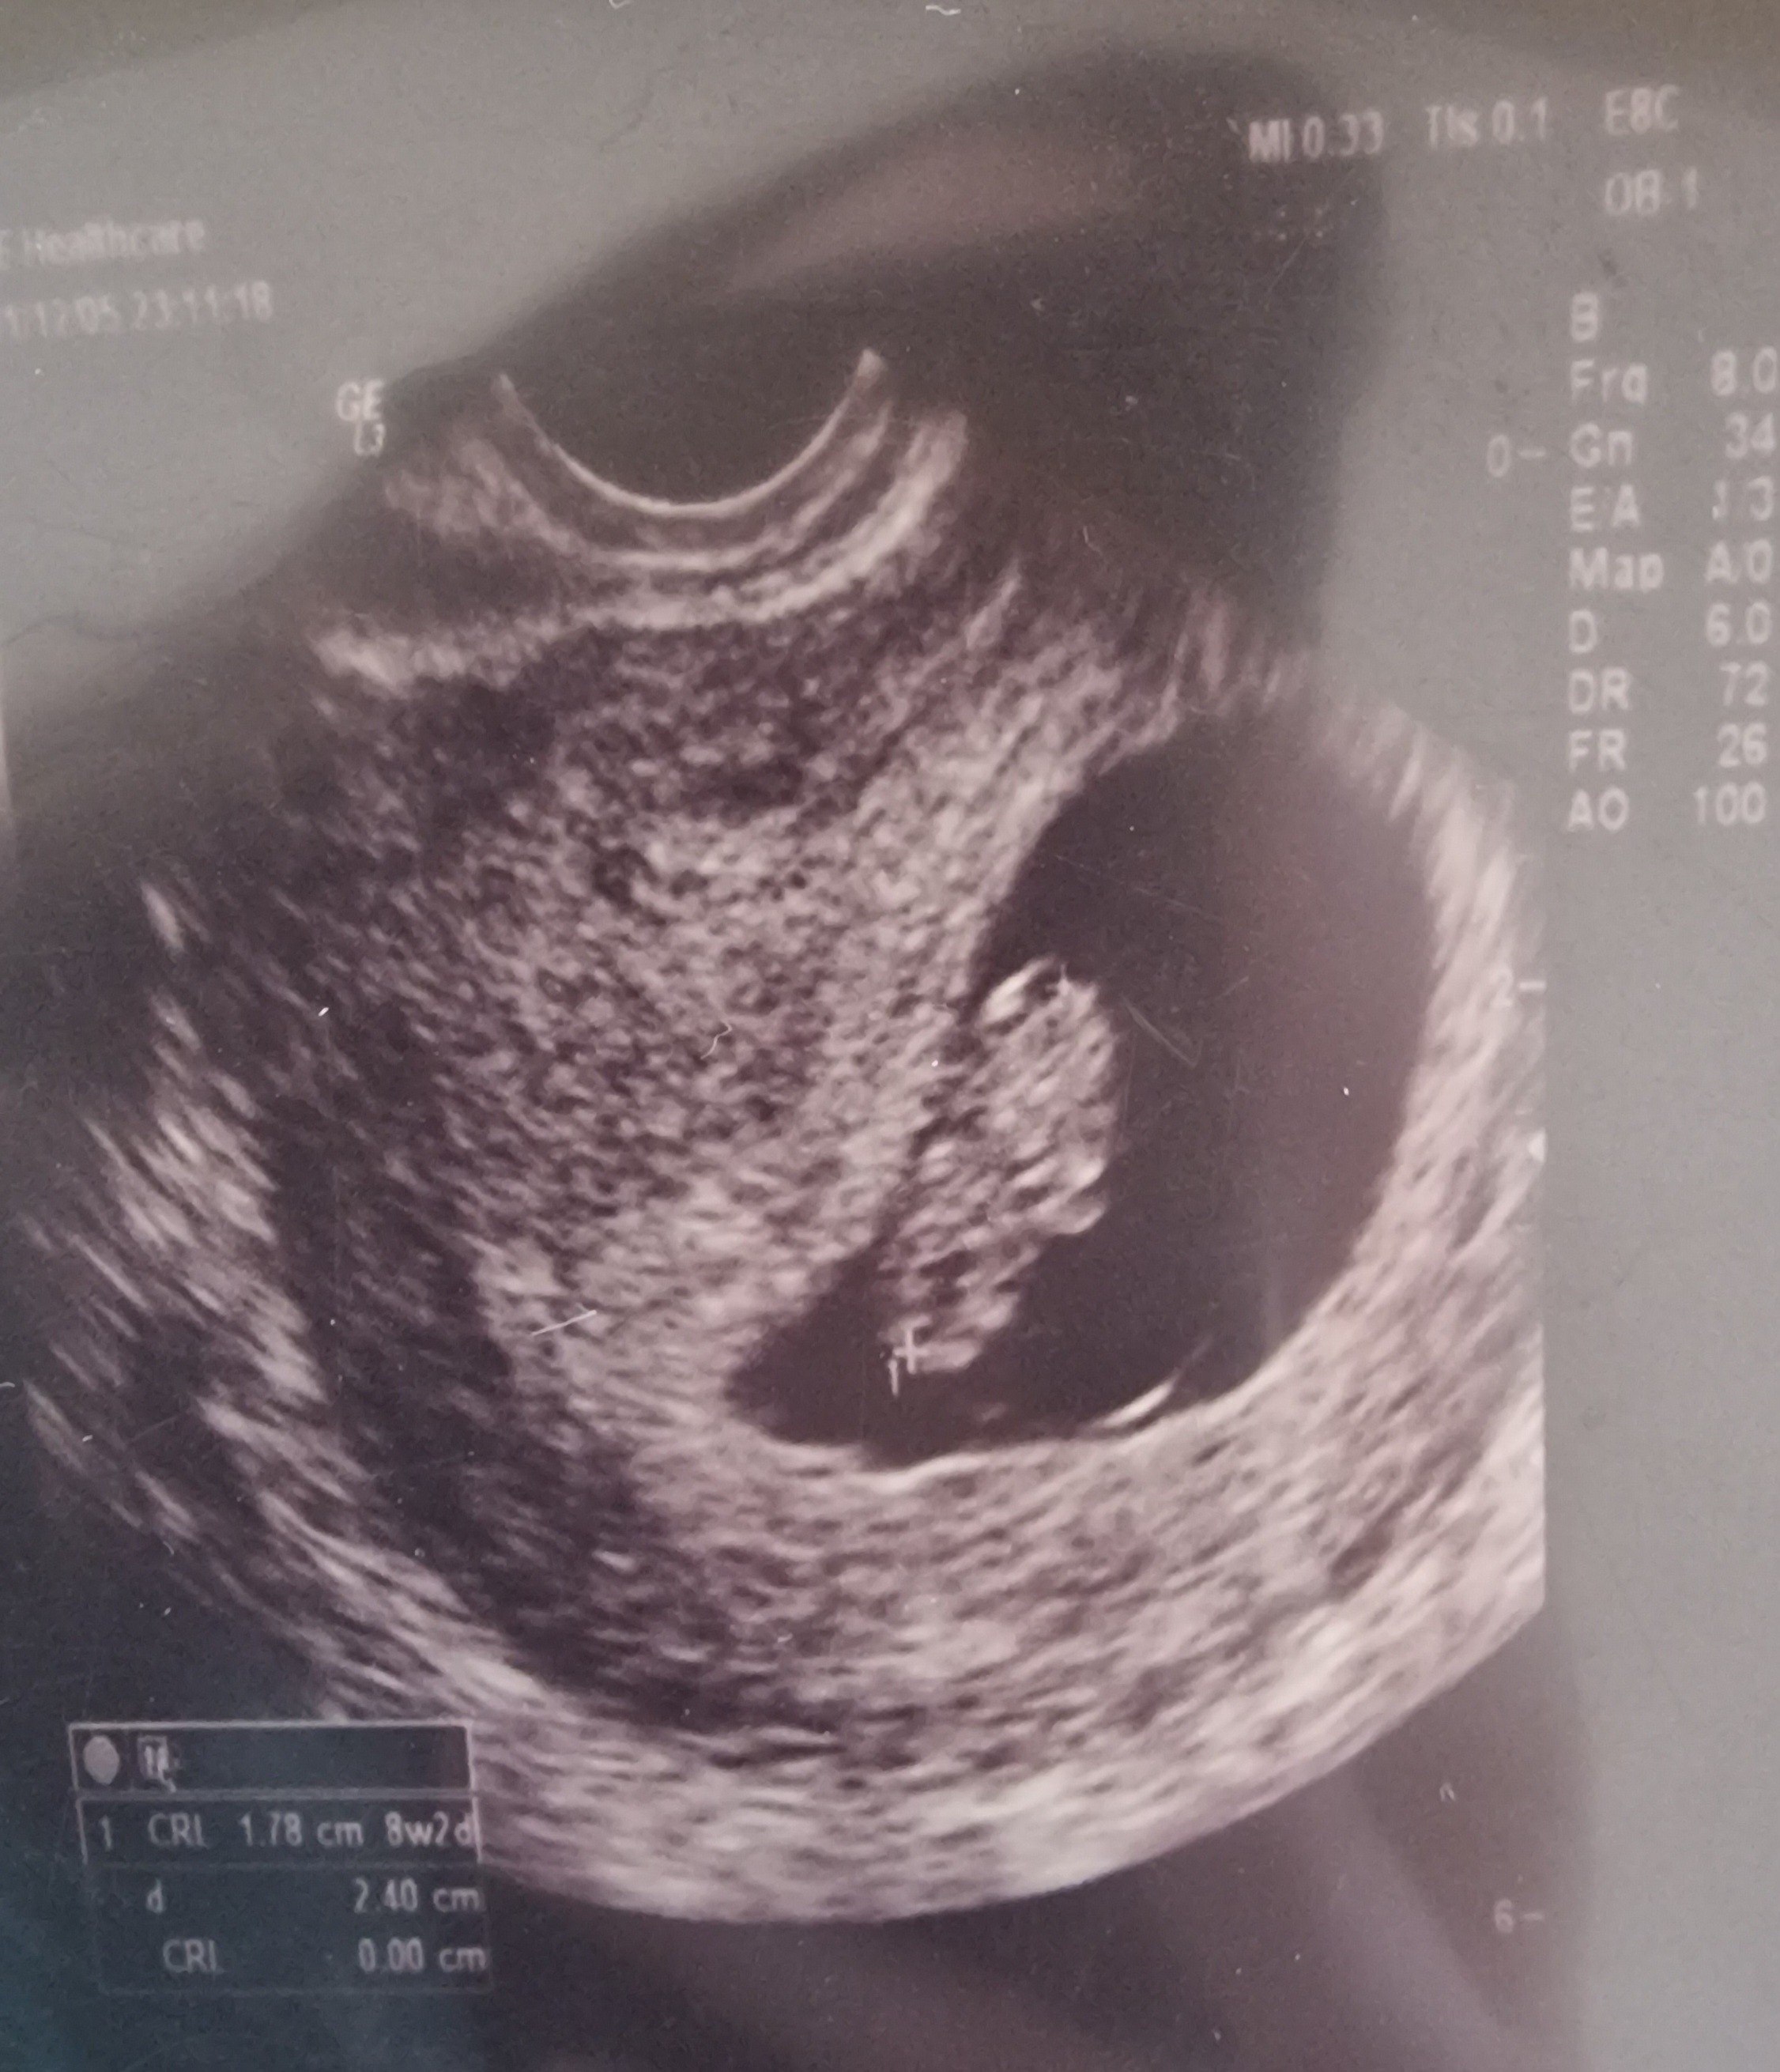

Hejka :) Ja już po wizycie, serduszko bije ❤️ Lekarka super i będę u niej prowadzić ciążę, więc z wizyty u mojego lekarza rezygnuję. Następna wizytę mam za 3 tygodnie, nie wiem jak ja wytrzymam tyle czasu.

Powiem Wam, że prawie zawał miałam na wizycie bo zmierzyła okruszka i pokazywało jej długość na 7+4, a tydzień temu w środę było 7+3, więc ja już prawie w płacz, że ciąża się zatrzymała. A ona mi pokazuje serduszko ❤️

Potem poszukała z innej strony i zmierzyła na nowo i pokazuje już 8+2.